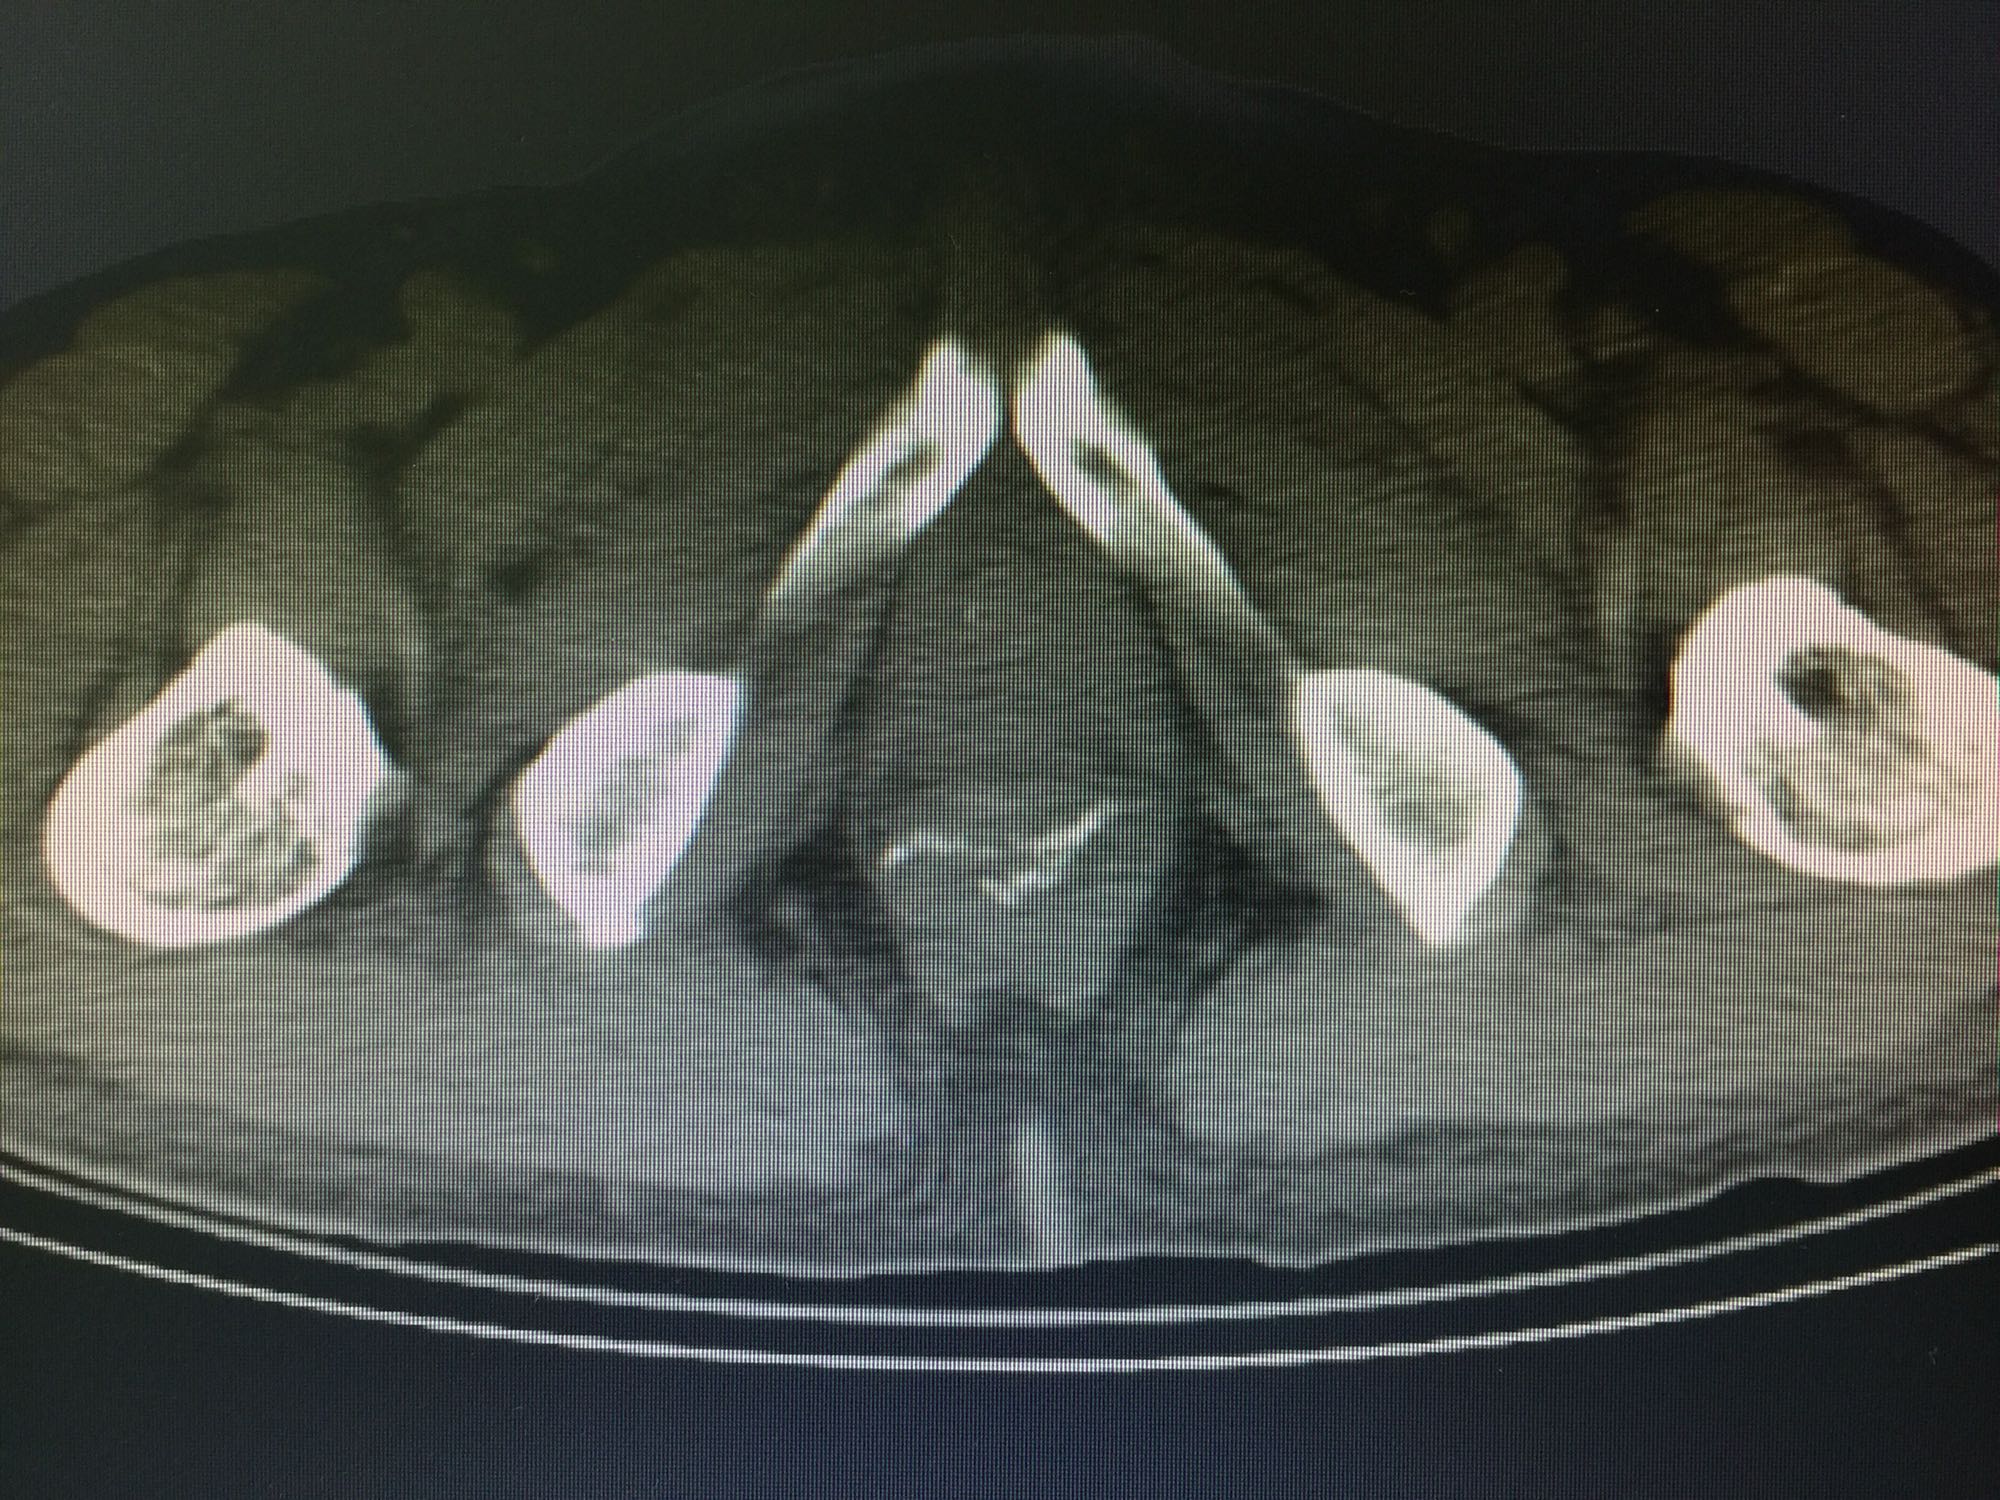

一般状态好,无贫血貌,周身浅表淋巴结不大;腹部平坦,无压痛,未及包块;肛门指诊:距肛缘5cm可及肿物下缘,质硬,活动差,不光滑。结肠镜报告:1:结肠癌,2:结肠息肉。如下图:

诊断:直肠癌,结肠息肉。 治疗:直肠低位前切除术,术后7天盆腔引流量逐渐增多,伴腹痛、发热,血像明显增高,腹部CT见腹腔大量积液,吻合口处结构不清晰,直肠旁间隙见条索状增强影;再次手术证实为吻合口漏。